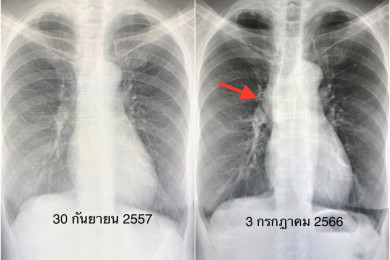

2 ในล้านคน! เผยเคสหญิง 66 ปี แข็งแรงดี ไม่ไอ ไม่เหนื่อย เอ็กซเรย์ปอดพบเนื้องอก